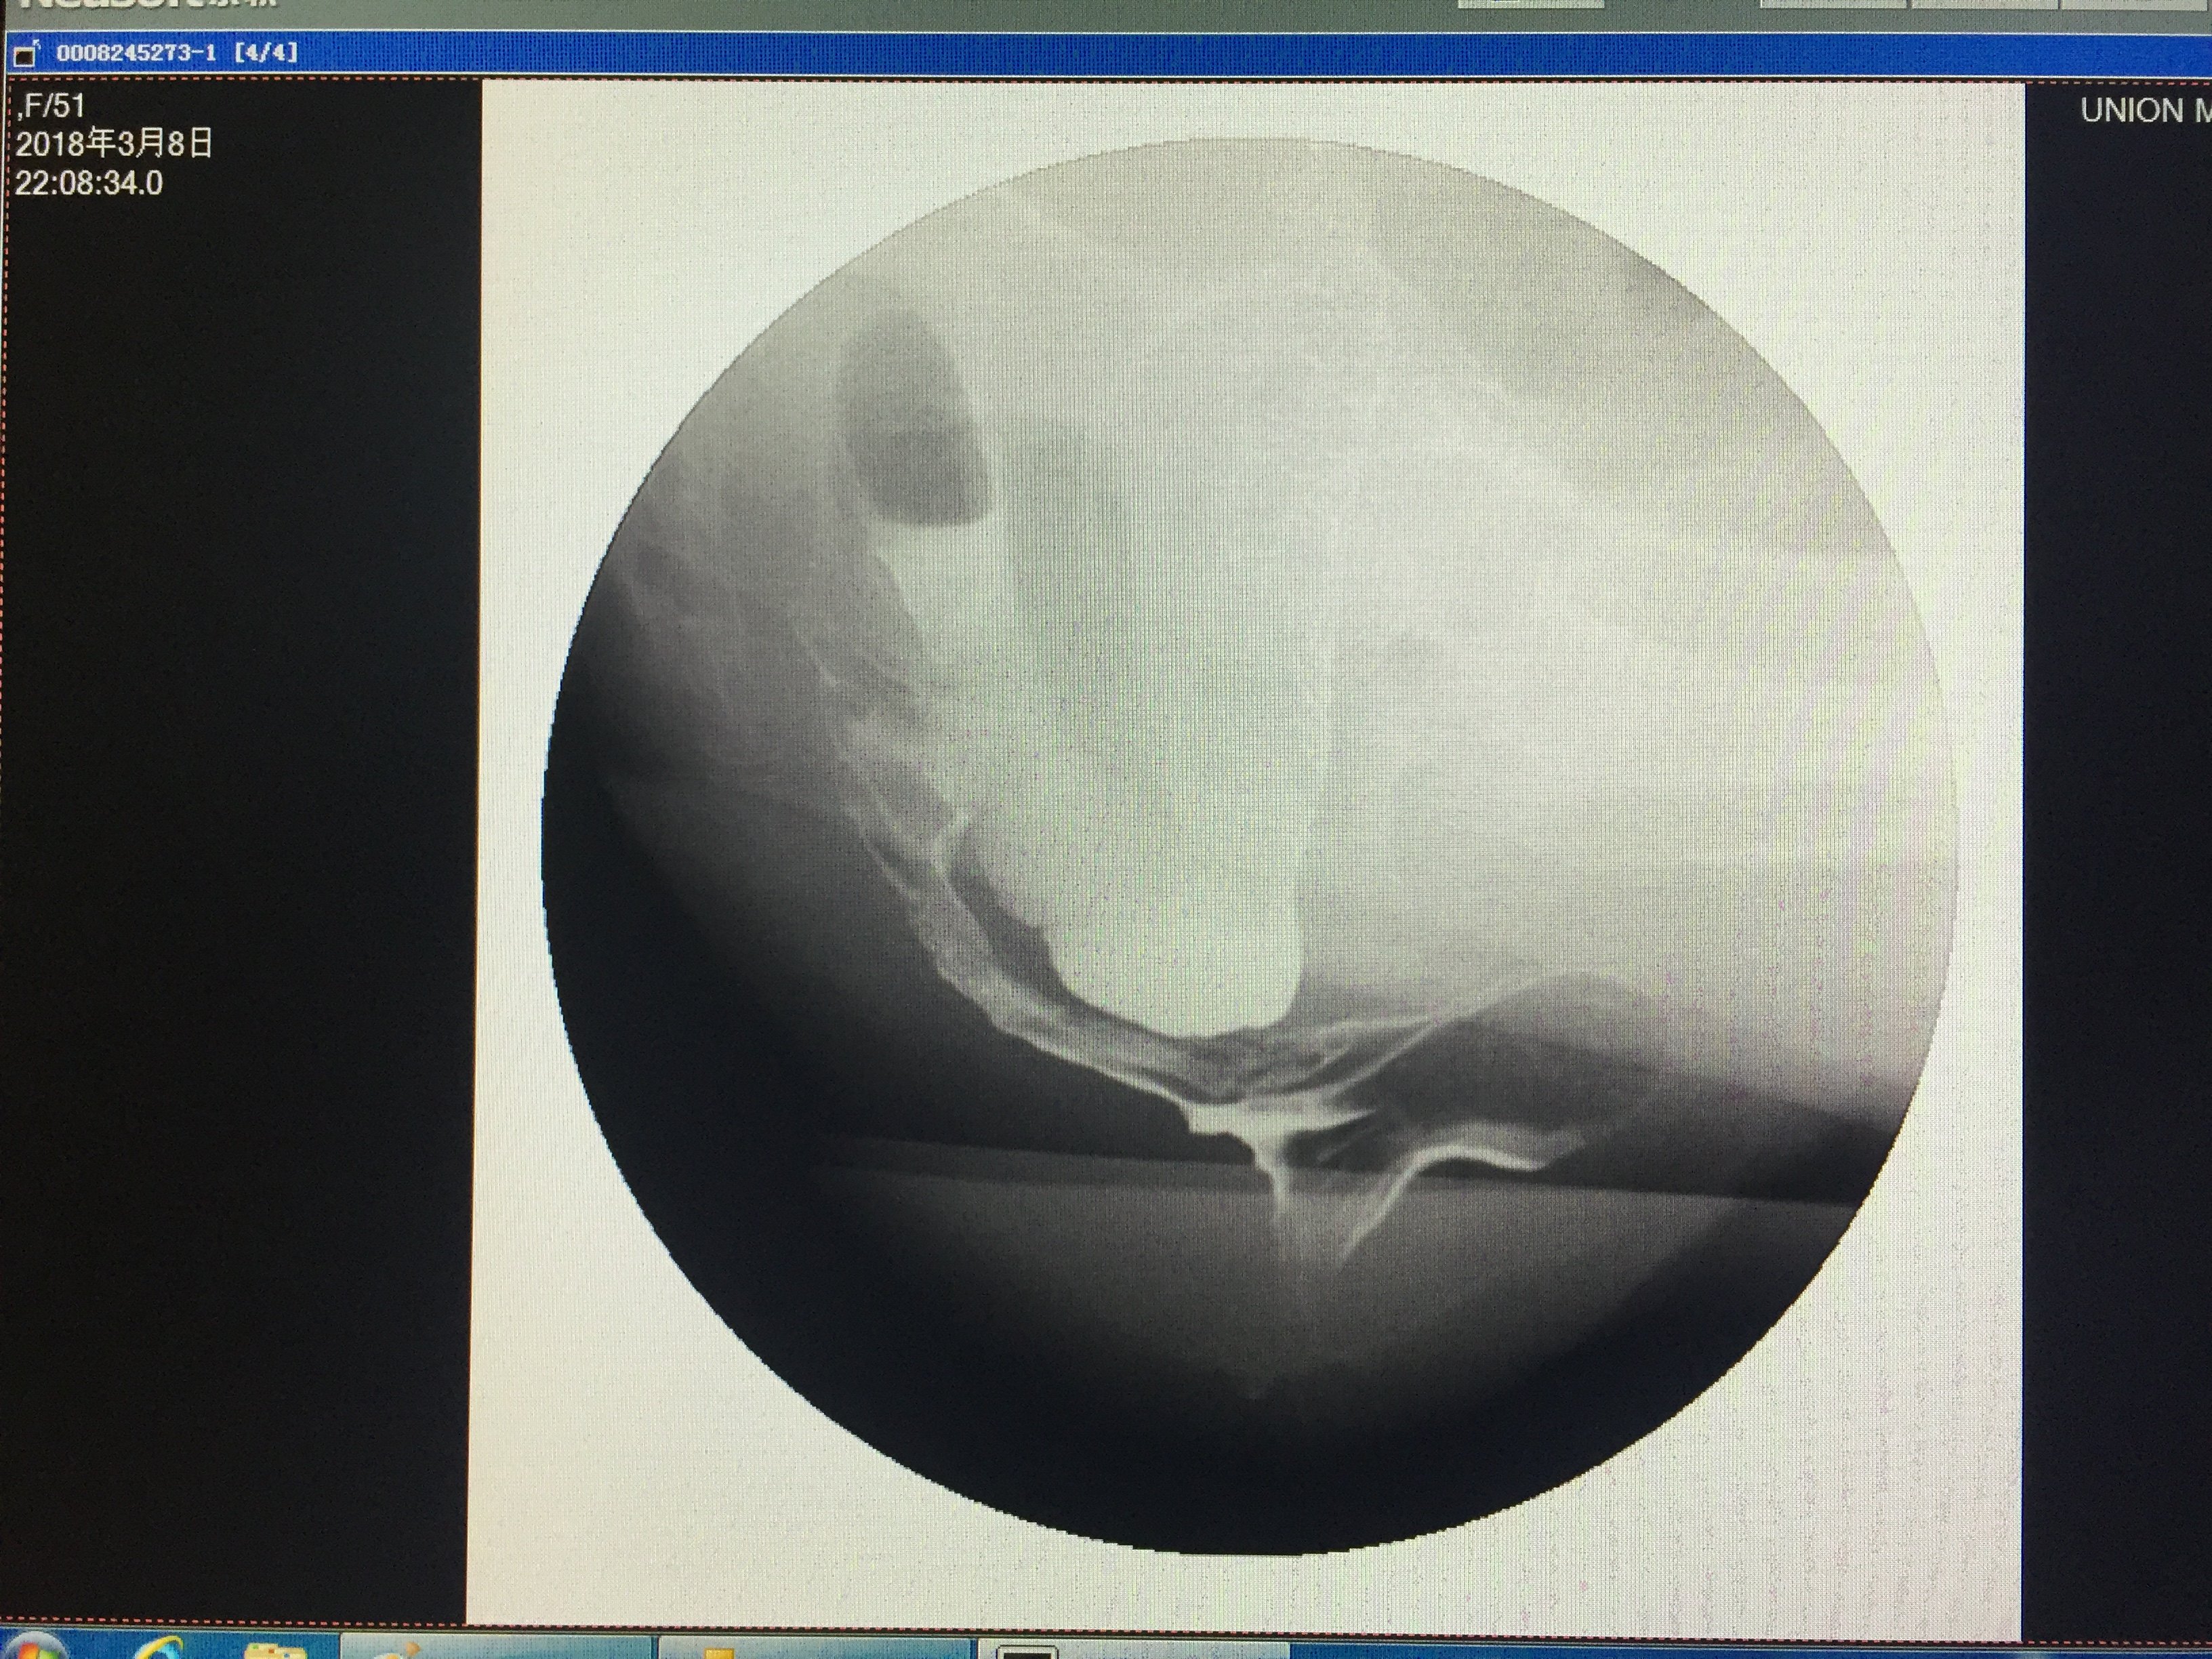

精品推荐医学影像诊断ppt课件图文详解完整版-急腹症影像诊断学